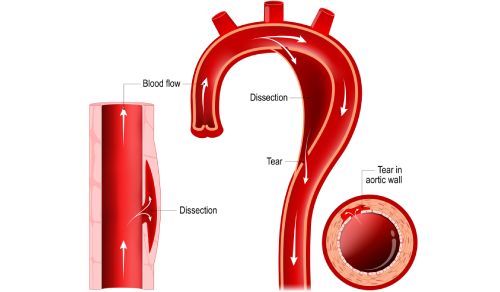

The patient’s severe thrombosis required months of multidisciplinary care and the transplantation of his liver, stomach, large intestine, small intestine, pancreas, and kidney.